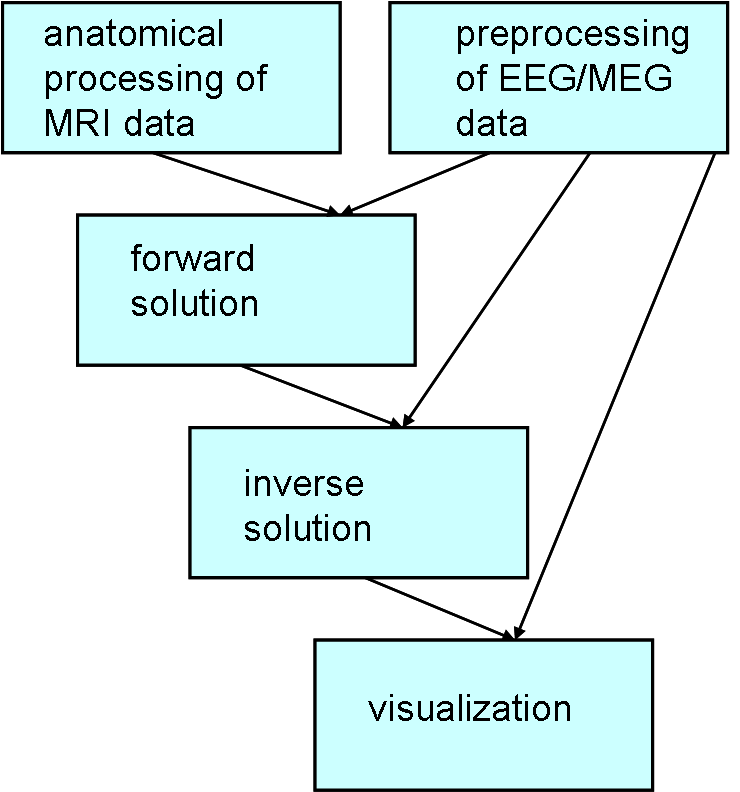

The pipeline of the MNE analysis can be divided into 5 bigger step

- Anatomical processing of MRI data. MNE software is using the output and some of the functions of FreeSurfer (FS).

- Preprocessing of EEG/MEG data. MNE calculates also the average and the noise-covariance matrix.

- Calculation of the forward solution.

- Calculation of the inverse operator.

- Visualization.

The last three steps are using the outputs from processing of anatomical and electrophysiological data.